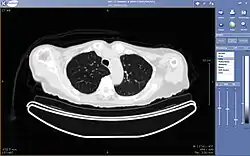

A picture archiving and communication system (PACS) is a medical imaging technology which provides economical storage and convenient access to images from multiple modalities (source machine types).[1] Electronic images and reports are transmitted digitally via PACS; this eliminates the need to manually file, retrieve, or transport film jackets, the folders used to store and protect X-ray film. The universal format for PACS image storage and transfer is DICOM (Digital Imaging and Communications in Medicine). Non-image data, such as scanned documents, may be incorporated using consumer industry standard formats like PDF (Portable Document Format), once encapsulated in DICOM. A PACS consists of four major components: The imaging modalities such as X-ray plain film (PF), computed tomography (CT) and magnetic resonance imaging (MRI), a secured network for the transmission of patient information, workstations for interpreting and reviewing images, and archives for the storage and retrieval of images and reports. Combined with available and emerging web technology, PACS has the ability to deliver timely and efficient access to images, interpretations, and related data. PACS reduces the physical and time barriers associated with traditional film-based image retrieval, distribution, and display.

Most PACS handle images from various medical imaging instruments, including ultrasound (US), magnetic resonance (MR), Nuclear Medicine imaging, positron emission tomography (PET), computed tomography (CT), endoscopy (ES), mammograms (MG), digital radiography (DR), phosphor plate radiography, Visible Light Photography (VL), Histopathology, ophthalmology, etc. Additional types of image formats are always being added. Clinical areas beyond radiology; cardiology, oncology, gastroenterology, and even the laboratory are creating medical images that can be incorporated into PACS. (see DICOM Application areas).